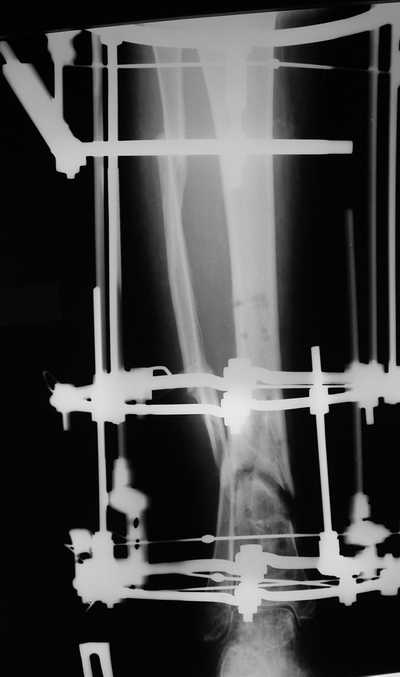

Женщина 46 лет, неудачно лечившаяся по поводу перелома голени в нижней 1\3

сначала в гипсе,  поступила через 6 месяцев после остеосинтеза пластиной

(рис 1). Имелась деформация в нижней 1\3 голени: варус, антекурвация,

наружная ротация, два свища. Удалена пластина, дебридмент мягких тканей,

остеотомия м\б кости, аппарат Илизарова. По рентгенограммам в двух проекциях